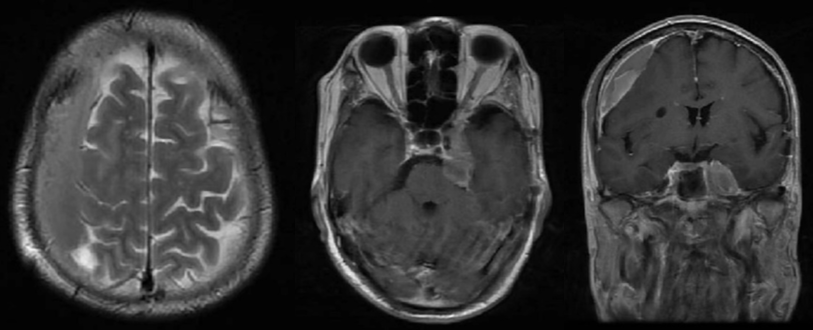

术后患者接受了伽马刀治疗。患者左眼视力明显下降。2024年3月因头部外伤复查,MRI检查提示右侧硬膜下血肿,左侧海绵窦肿瘤明显增大(图3)。当时予以阿托伐他汀保守治疗。

2024年7月复查头颅MRI提示硬膜下血肿已吸收,左侧海绵窦肿瘤快速增大(图4)。